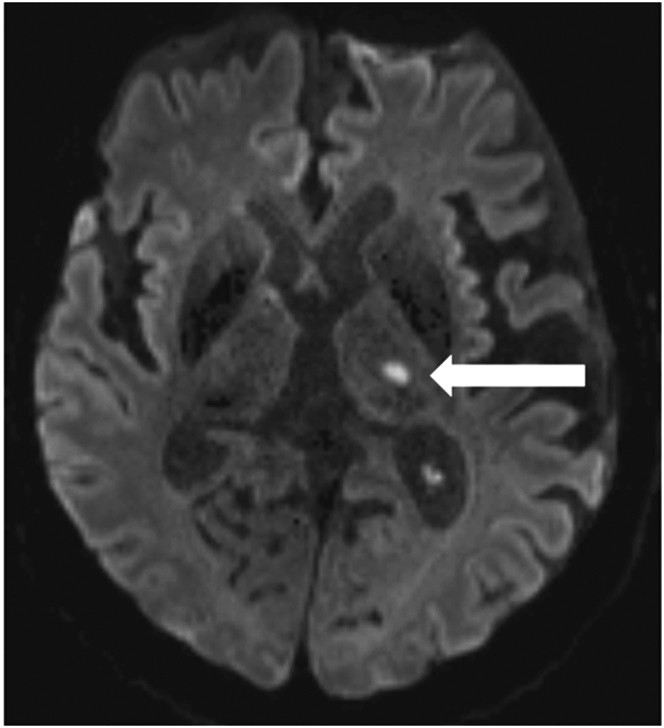

Ursache ist eine als ischämie bezeichnete plötzliche minderdurchblutung des gehirns und damit eine minderversorgung mit sauerstoff und glukose die zur energiegewinnung benötigt werden. Mrt beim akuten ischämischen schlaganfall. Giovanni defilippo hausarzt. Mini med studium mit prim.

Mrt Nach Schlaganfall Mri After Ischemic Stroke Youtube